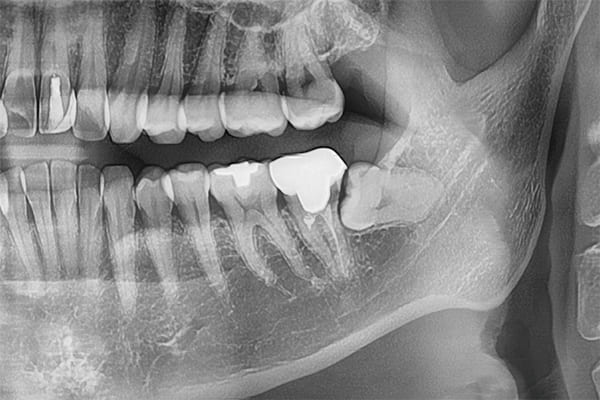

パノラマレントゲンデータ

精密なCTデータで状態把握

親知らず抜歯の症例ケース

親知らずが横向きに生えていて、隣の歯を圧迫している埋伏歯の抜歯ケースです。このタイプは、抜歯が難しい分類になります。

当院では、このような難しい親知らずの抜歯ケースでもなるべく腫れずに、痛くなく抜歯することが可能です。